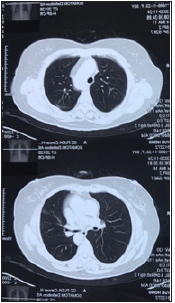

The patient first visited our outpatient clinic on July 2020 to seek medical consultation regarding her condition with the manifestation of shortness of breath, accompanied with chest oppression and chronic productive cough. Upon consultation, an herbal prescription, mainly comprised of Codonopsis Pilosula (Dangshen), Glehniae Radix (Beishashen), Ganoderma (Lingzhi), Sinapis Semen (Baijiezi), Pinellia Ternata (Banxia), Hedyotis Diffusa Willd (Baihuasheshecao), Viola Philippica (Zihuadiding), Agrimoniae Herba (Xianhecao), Solanum Nigrum (Longkui) and Astragali Radix (Huangqi) was prescribed to her for the duration of six months. The patient then went for a CT-screening on November 2020, in which her CT images indicated no obvious ablated lesion with the absence of exudative infiltration at all three of her previous ablation zones. Tissue’s damage resulted from the procedure was also fully recovered and no nodule was observed as shown in Figure 3 & 4. Her previous complaints of shortness of breath, chest oppression and chronic cough were significantly improved as well.

Figure 3:No ablated lesion was observed on the right upper lobe and left upper lobe of the lungs.

Figure 4:No ablated lesion was observed on the left lower lobe of the lungs.